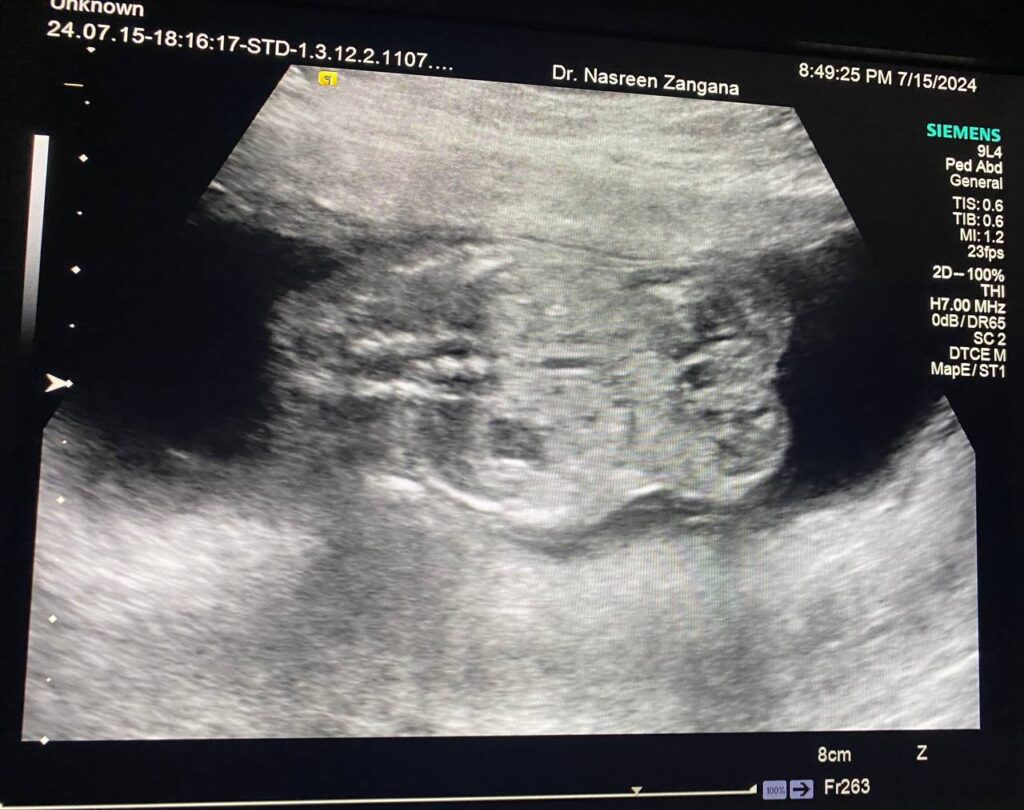

Fetus , right kidney Polycystic?

When 14-15 weeks